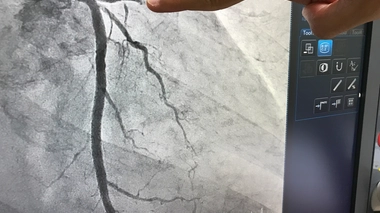

Cathétérisme cardiaque, coronarographie... ces nouveaux examens du cœur à l'hôpital général de Douala

L'angiographie et le cathétérisme cardiaque sont désormais possibles à Douala